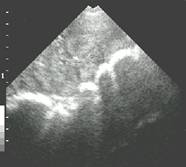

Non-pregnant uterus Ovarian Follicles and uterine outline Sow in estrus